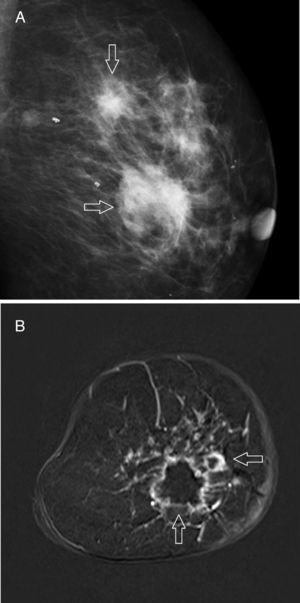

The most common mammographic findings (61–80 per cent) are pleomorphic microcalcifications,45 or thin ramified lines,46 that in most of the cases associate a mass with spiculated edges43,45 (Fig. 4A). Its common appearance in the ultrasound is that of an irregular hypoechogenic mass,45 or microlobulated or angular edges, with an abrupt interphase,43 and posterior acoustic reinforcement46; on the other hand, it manifests itself as a lesion without a detectable mass in the ultrasound – an event that occurs more frequency with this subtype than with other subtypes. The MRIs usually show one mass of irregular morphology, with speculated or irregular edges that appears hypointense or isointense in the T2-weighted images, and with heterogeneous internal enhancement44 (Fig. 4B); the dynamic study with contrast shows rapid initial enhancement with posterior washout.41,46

Triple negativeIt represents 12–17 per cent of breast cancers only,47 but it is responsible for a high percentage of deaths due to its aggressiveness.48 Its incidence is higher in Afroamerican younger women who are carriers of a BRCA1 gene mutation. They are usually unifocal neoplasms49 that when diagnosed reach larger sizes, with common axillary metastases, high histological grade, and no direct correlation between tumour size and survival,50 or the probability of axillary infiltration.49 The risk of relapse is higher during the first 1–4 years of follow-up, above all in lungs and brain,47 but from the 10th year onwards, the risk of relapse drops to a lower level than that of patients with tumours expressing oestrogen receptors.51 Unlike the rest, its sensitivity to neoadjuvant chemotherapy is higher, and prognosis looks better after a complete response.52 Many interval cancers correspond to this subtype,53 most of which are detected clinically, which has been associated with rapid tumour growth and high breast density in the mammography – more common at younger ages.

In the mammography, the most characteristic pattern is an oval, lobulated, or round mass with poorly established edges and without associated microcalcifications45,54 (Fig. 5A); irregular shapes and spiculated edges53 are less common. In the ultrasound it usually looks like an irregular hypoechogenic mass of heterogeneous structure43; however, in 15–20 per cent of the patients its appearance may be misleading and initially lead us to think of benignity,55 since it shows a round or oval shape, well established edges,45,53 and posterior acoustic reinforcement.43 The most common findings in the MRI40,41,44,55,56 are a round or oval mass with well established edges (39–71 per cent), that show intratumor hyperintensity in the T2-weighted sequences due to the existence of intratumor necrosis (46–66 per cent), showing ring enhancement pattern in 46–80 per cent of the cases (Fig. 5B), while exhibiting kinetic behaviour in plateau or with washout.